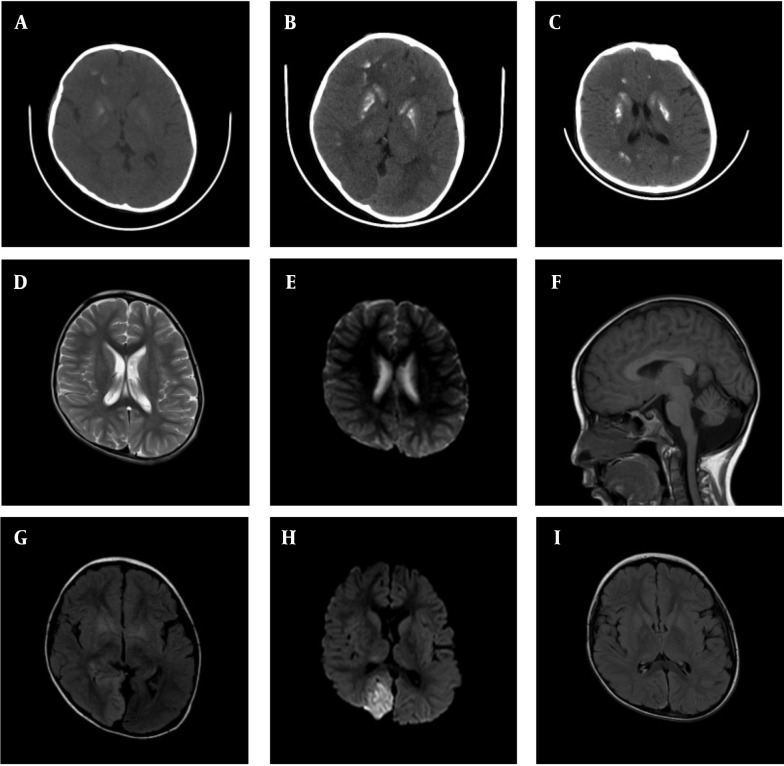

Case presentation: Here, we report the case of a child who initially presented with vomiting and convulsions. Blood gas analysis revealed significant hyperlactatemia and hypocalcemia. The child's urinary calcium level was markedly decreased, measured at 0.15 mmol/24h, well below the normal range. A brain CT scan showed symmetrical calcification in the bilateral basal ganglia. Endocrine testing confirmed low parathyroid hormone (PTH) levels. During hospitalization, the child received treatment for recurrent seizures, including midazolam and levetiracetam. One month post-discharge, the child was readmitted due to elevated lactate levels. Genetic testing confirmed the diagnosis of MELAS syndrome, identifying the m.3243A > G mutation in the MT-TL1 gene. Under symptomatic treatment, the child has not experienced any further convulsions and has been regularly followed up at our hospital.

Conclusions: This case underscores the importance of considering MELAS syndrome in patients presenting with hypoparathyroidism. Effective management of epileptic seizures and maintaining an appropriate calcium-to-phosphorus balance are crucial for minimizing brain damage and improving the patient's prognosis.